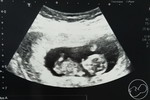

เบาหวานขณะตั้งครรภ์

แม่ๆบ้านไหนเคยเป็นเบาหวานขณะตั้งครรภ์บ้างคะ จะอันตรายกับลูกมากไหมและต้องดูแลตัวเองอย่างไรบ้างคะ แม่บ้านนี้34+3 ท้องแรกค่ะ #ทีมมิถุนา64